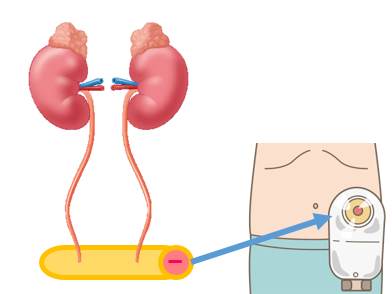

究める鏡視下膀胱全摘術・尿路変向術 Level up LRC, RARC | 三木。メジカルビュー社|泌尿器科|究める鏡視下膀胱全摘術・尿路変向。ロボット支援膀胱全摘除術(RARC) | 岩手医科大学 泌尿器科学講座。★3月精米★ 令和6年産 福井県産 いちほまれ 5kg 白米 精米。膀胱がん【泌尿器科疾患について】 - 東京慈恵会医科大学 泌尿器科。膀胱がん|KOMPAS。手術手技(膀胱全摘除術) | 領域情報 | アステラスメディカルネット。膀胱がん|KOMPAS。周術期の負担を軽減し早期社会復帰を!「ロボット支援腹腔鏡下。腎盂尿管移行部狭窄症に対するロボット支援腹腔鏡下腎盂形成術。朝倉書店『内科学』(第12版)デジタル付録。腹腔鏡下尿膜管摘出術及び左腎摘出術 - Olympus Professional。ロボット手術の定番!新品、未使用です。間違って2冊買ってしまったので、ページを開いてもいないため、本屋さんの「売上スリップ」も付いたままの全くの新品です。膀胱がんの外科治療について | 小野薬品 がん情報 一般向け。